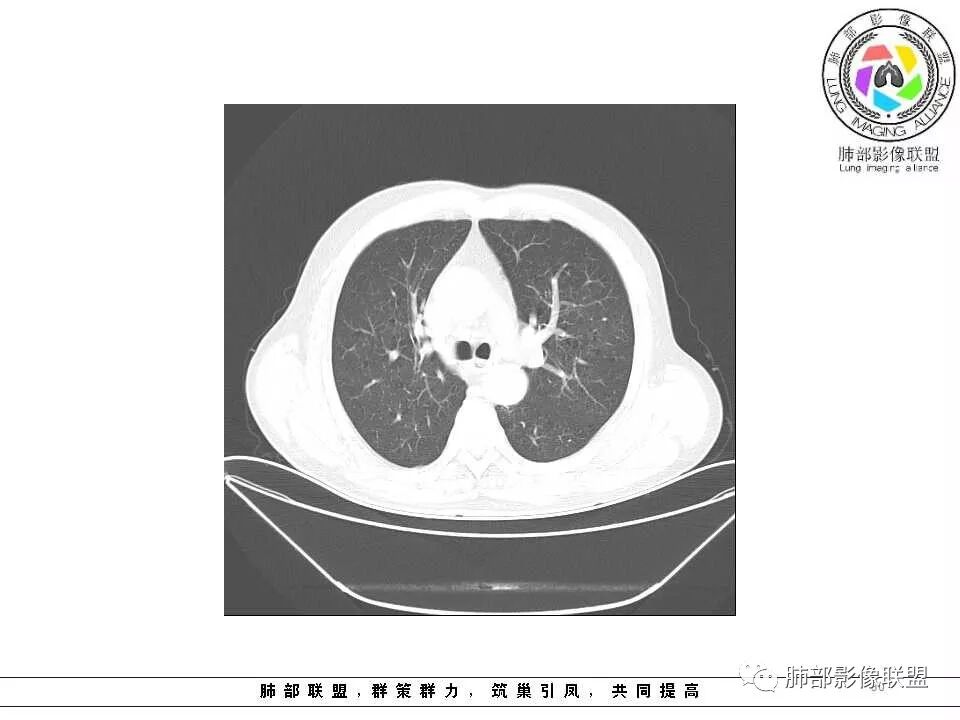

影像学特点:肺气肿背景下在大概一年的时间里出现了一个光滑的小结节,因为图像给的不是太薄,与支气管的关系判断不清,从结节周围出现斑片状炎症来判断,应该考虑结节位于支气管内,周围是阻塞性炎症,这样比较容易解释咯血

老年男性,左肺舌段见多个小结节灶及斑片状高密度灶、磨玻璃影,结节灶边界清晰,光滑,无明显分叶,密度均匀,周围病灶密度不均,一年内生长,考虑恶性肿瘤并阻塞性肺炎出血,小细胞可能大。

老年男性,肺气肿背景,左肺上叶舌段病灶明显增大,变异膨隆,远端阻塞肺炎,考虑鳞癌。

老年男性,肺气肿基础。约一年时间出现左肺上叶舌段支气管近端结节影,远端斑片样阴影,边缘模糊。考虑近端恶性占位,远端有阻塞性炎症。

老年男性,有咳血病史,左肺上叶舌段一年时间出现新发类圆形小结节,感觉在支气管内,部分凸出气管外,没有mpr不好说,远端肺野斑片模糊影,考虑阻塞性炎症,纵隔无明显肿大淋巴结,小细胞代排,按照发展速度,类癌低度恶性,应该发展缓慢,一年病史,代排,首先考虑鳞癌并阻塞性炎症

肺气肿背景,2016年左肺上叶上舌段见微结节,2017年5月左肺结节增大,密度均匀,边缘光滑锐利,与邻近血管关系密切,血管贴壁走行,外侧见尖状突起,下舌段片状影,沿着支气管走行,内有粘液栓,考虑鳞癌,鉴别小细胞肺癌。

肺气肿背景,2016年左肺上叶上舌段见微结节,一年后左肺结节增大,密度均匀,边缘光滑、膨隆,似见小分叶,下舌段片状影,沿着支气管走行,内,老年患者,咯血1月。考虑恶性病变并阻塞性肺炎,鳞癌?注意鉴别结核。

左肺上叶舌段支气管管壁略增厚 间隔一年 管壁增厚明显 向腔外突出形成结节 管腔闭塞 远端片状及斑片影 纵隔淋巴结增大 肺气肿背景 考虑鳞癌伴阻塞性炎症可能

老年男性,咯血1月,肺气肿背景,16年左肺上叶舌段结节,左肺门疑似淋巴结肿大,呈结节感。17年左肺上叶舌段见沿支气管走行分布结节 远端阻塞性肺炎,左肺门淋巴结肿大明显,首先考虑恶性病变,鳞癌?类癌?

老年男性,肺气肿背景,左肺上叶舌段一年前小结节后长大,实性,与邻近气管关系密切,远端有少许小片状炎症类小结节状,左肺门淋巴结肿大,首先考虑恶性,鳞癌可能性大,代排小细胞癌。病灶下方斑片状影,考虑炎症。

老年男性,咯血一个月,有慢支病史。左肺上叶舌段可见一类圆形结节影,边缘光滑,远端有片条状影,一年前胸ct基本正常。感觉还是考虑肺癌合并阻塞性炎症。鳞癌还是小细胞?